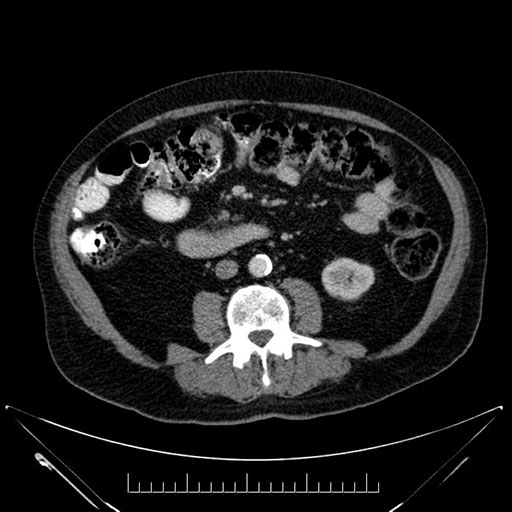

Whipple (pancreaticoduodenectomy) [case 7]

Imaging Analysis

Look through the patient's CT scan to identify any areas of concern for the necessary procedure.

Based on your CT findings, which issue(s) would give reason for "planned slowing down moment(s)" in this case?

Considering a standard Whipple procedure, what step(s) of the operation would you do differently in this case?